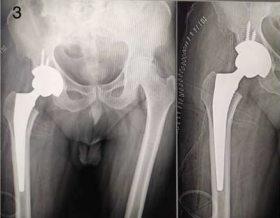

Interestingly, AVN of the hip was more frequently observed on the right side (50%) compared to the left (41.67%) and bilateral presentation (8.33%) among patients with a history of COVID-19. Figures 1 and 2 describe Plain X-rays of pelvis with both hip joints of a 51 year old male and a 43 year old male, having stage 4 AVN of hip, involving the right and left sides respectively. Figures 3 and 4 represent the post-operative X-rays of the above mentioned patients after uncemented THR on the respective sides.

Figure 3: Post-operative X-ray of right hip AVN after uncemented THR on right side.

Figure 4: Post-operative X-ray of left hip AVN after uncemented THR on left side.

Figure 3

Figure 4